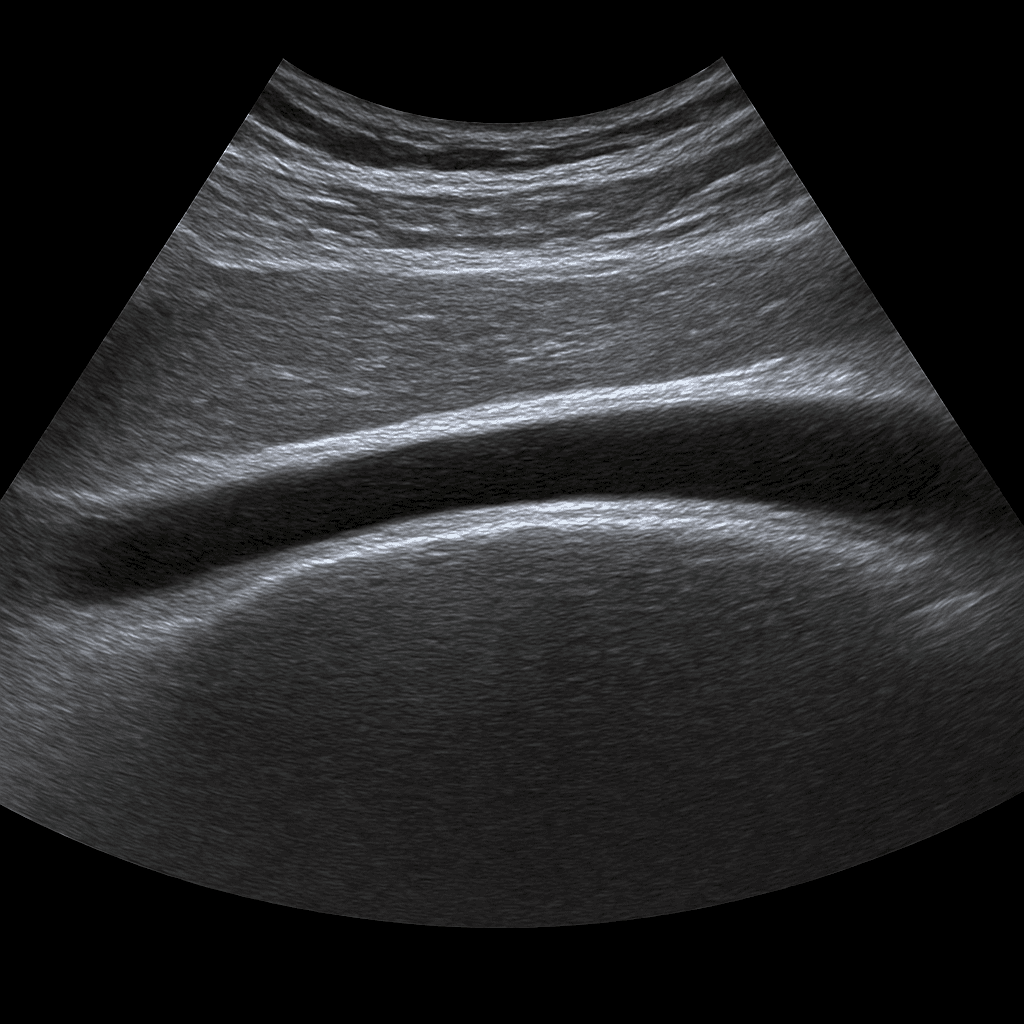

Ultrasound of the Achilles tendon – examination of the Achilles tendon and its attachments

An ultrasound of the Achilles tendon is used to assess the structure, blood circulation and surrounding tissues of the Achilles tendon. The examination is performed by a specialist in radiology and provides detailed images in real time of the condition of the tendon. It can detect any inflammation, ruptures, calcifications or scarring that causes pain or impaired function in the foot.

The examination is performed while you are lying or sitting with your foot slightly bent. A gel is applied to the skin to provide optimal contact between the probe and the skin. The doctor moves the ultrasound probe along the Achilles tendon and assesses the structure in both longitudinal and cross-sectional views. If necessary, dynamic movements can be performed to see how the tendon reacts to load.